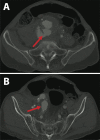

There is a growing body of literature expanding the indication of endovascular aneurysm repair, from prophylactic treatment of aneurysms to other indications such as ruptured and complicated ruptured abdominal aneurysms. Concomitant aortocaval fistula is rare, and reports of open and endovascular repair exist. We report a unique hybrid approach to a case of a ruptured abdominal aortic aneurysm with aortocaval fistula, repaired primarily via endovascular approach in a hybrid, two-staged fashion. Representative images are presented in addition to a short review of this pathology.